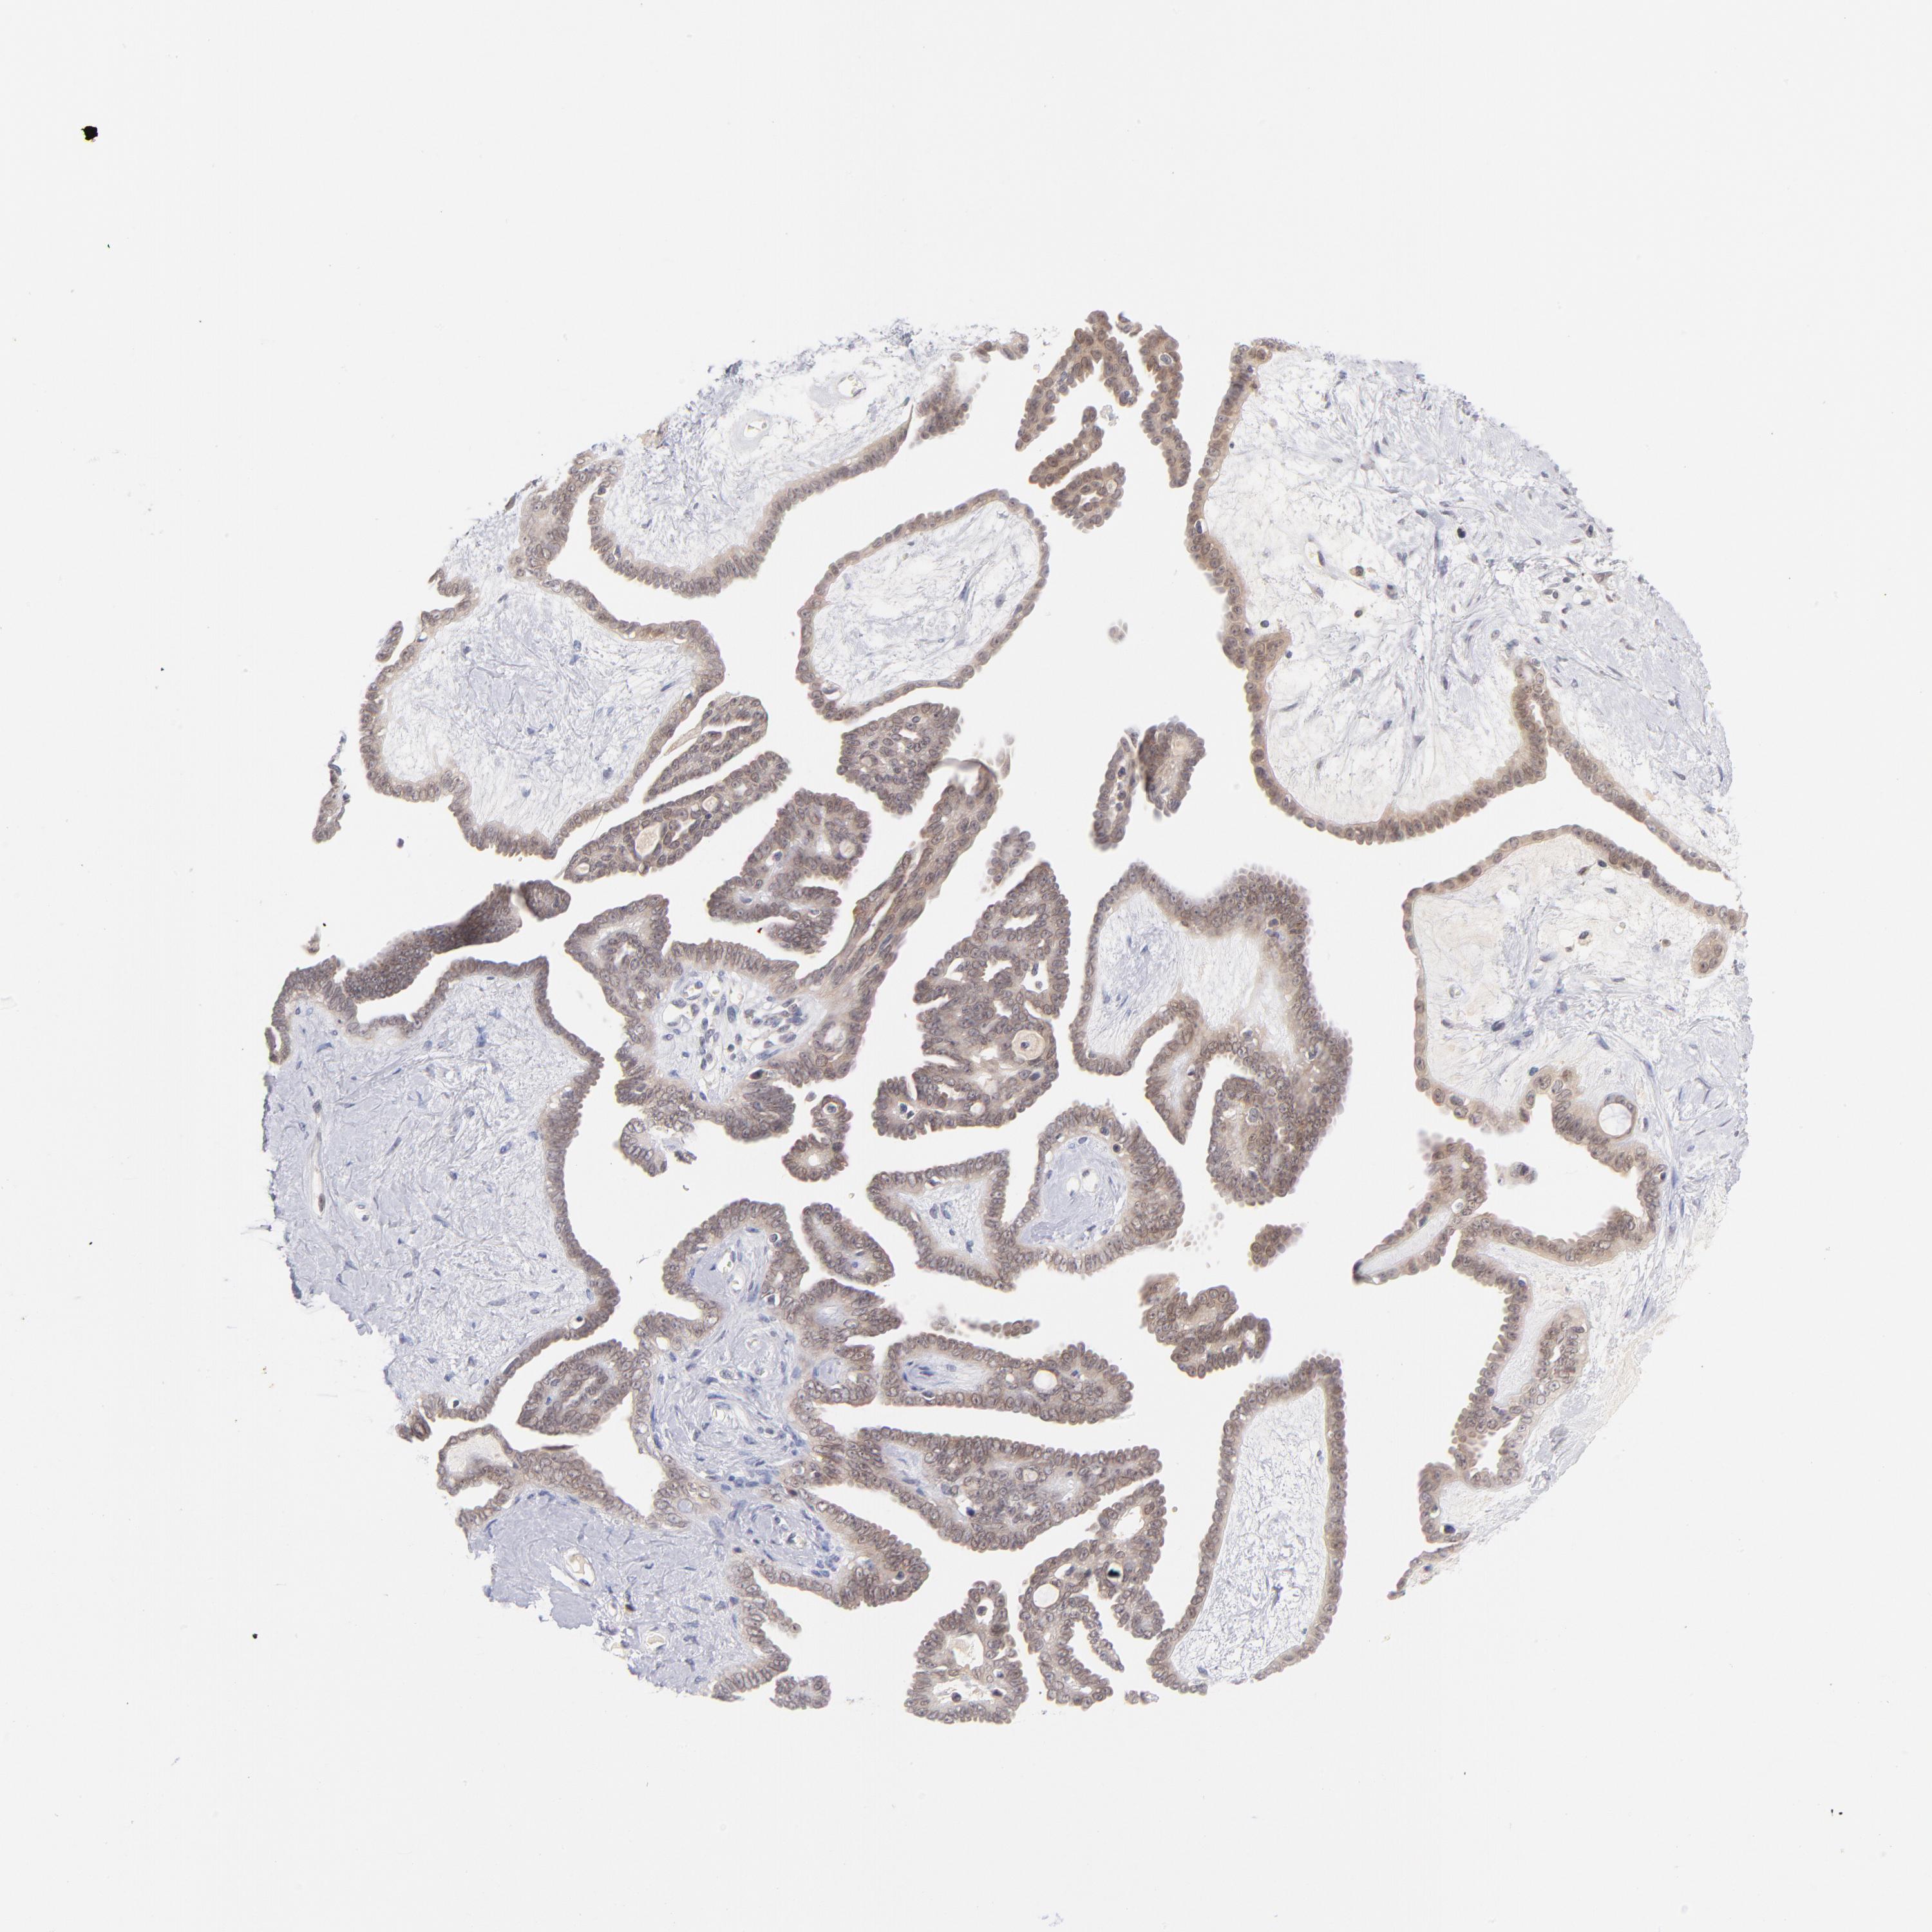

OVARIAN CANCER - Protein expressioni

A mouse-over function shows sample information and annotation data. Click on an image to view it in a full screen mode. Samples can be filtered based on level of antibody staining by selecting one or several of the following categories: high, medium, low and not detected. The assay and annotation is described here.

Note that samples used for immunohistochemistry by the Human Protein Atlas do not correspond to samples in the TCGA dataset.

Antibody stainingi

Antibody staining in the annotated cell types in the current human tissue is reported as not detected, low, medium, or high, based on conventional immunohistochemistry profiling in selected tissues. This score is based on the combination of the staining intensity and fraction of stained cells.

Each image is clickable and will lead to virtual microscopy that enables deeper exploration of all samples and also displays staining intensity scores, fraction scores and subcellular localization as well as patient and tissue information for each sample.

Antibody HPA024303

Carcinoma, endometroid